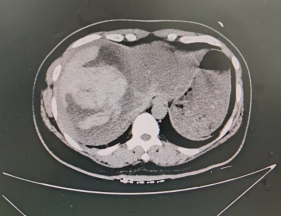

正在加班的介入中心李建军主任看过患者影像资料(图一)后,明确诊断患者肝出血,必须立即手术!然而,一个棘手的问题摆在面前:患者正处于月经期,介入栓塞术后再次出血和感染的风险会显著增高。但如果不紧急手术,一旦肝包膜下出血破裂,患者将很难存活。在与家属充分沟通、综合权衡利弊后,急诊介入栓塞术被确定为挽救段女士生命的唯一最优选择。与此同时,导管室的医护团队在崔雄伟主任和井学敏护士长的统筹安排下,宋丽波护士及杜宁技师已紧急就位,术前准备工作紧锣密鼓、有条不紊地推进。